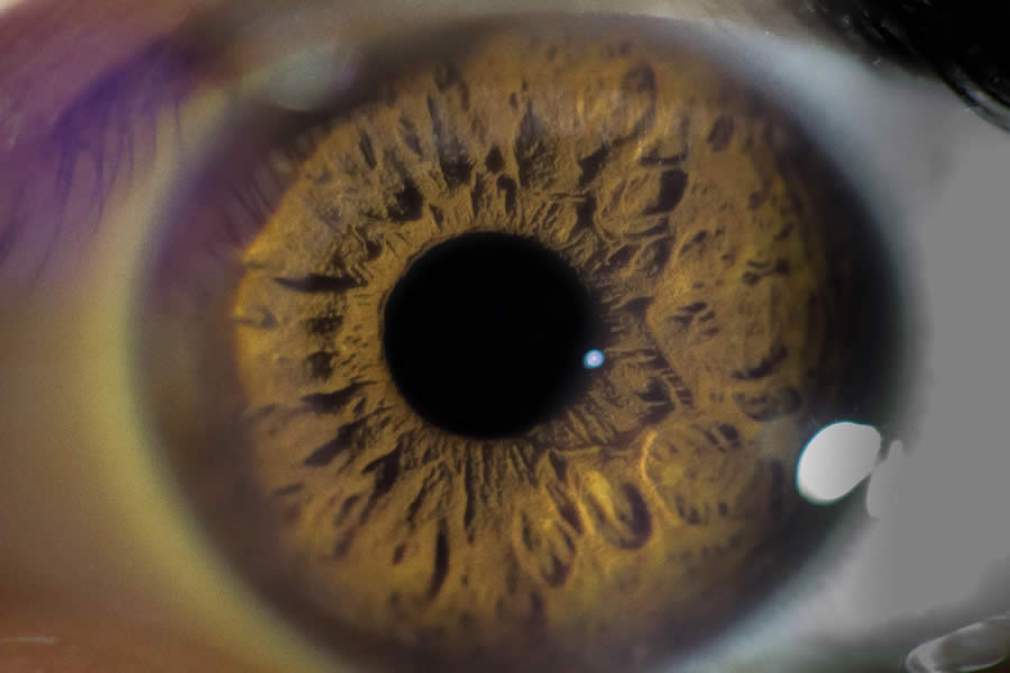

Em meio à pandemia do novo coronavírus (Covid-19), os cuidados com a saúde em geral não podem parar, inclusive os relacionados aos olhos. Abril Marrom é a campanha realizada por instituições e profissionais de saúde esse mês dedicada ao alerta do combate à cegueira. De acordo com o Conselho Brasileiro de Oftalmologia (CBO), o Brasil possui 1,2 milhão de cegos. São mais de 6 milhões de brasileiros com alguma deficiência visual. As causas são variáveis e, na maioria dos casos, a perda da visão poderia ter sido evitada com prevenção e diagnóstico precoce.

É possível evitar – Conforme afirma o Dr. Renan Ferreira Oliveira, especialista em catarata e cirurgia refrativa do Hospital de Olhos Sadalla Amin Ghanem, empresa do Grupo Opty em Joinville (SC), 80% das causas de cegueira são evitáveis. “Uma vez detectadas precocemente, tais condições podem ser tratadas em fases iniciais, evitando perdas irreversíveis da visão”, reforça o médico sobre a importância das visitas anuais ao oftalmologista em todas as faixas etárias. Os cuidados começam ainda na maternidade, com o teste dos olhinhos.

As principais patologias que levam a cegueira não-reversível são: glaucoma, retinopatia diabética e degeneração macular relacionada a idade (DMRI). A catarata, importante causa de baixa visão ou cegueira, é reversível com a cirurgia de facoemulsificação. Tais condições afetam principalmente pessoas acima de 60 anos, porém também podem aparecer precocemente em pacientes com fatores de risco. No adulto jovem, as causas predominantes incluem: trauma ocular, descolamento da retina e as doenças neurológicas e degenerativas, como a neurite óptica.